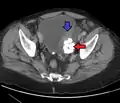

- Los divertículos vesicales son crecimientos en forma de globo en la vejiga comúnmente asociados con obstrucción crónica del flujo de salida, como hiperplasia benigna de próstata en hombres mayores. Por lo general, se encuentran en pares en lados opuestos de la vejiga. Los divertículos de la vejiga a menudo se extirpan quirúrgicamente para prevenir infecciones, rupturas o incluso cáncer.

Divertículo de la vejiga urinaria de un hombre de 59 años, plano transversal -